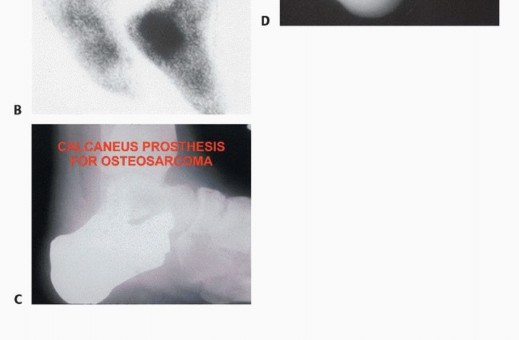

- الساركوما العظمية (Osteosarcoma): سرطان يبدأ في العظام، وهو من أكثر سرطانات العظام الأولية شيوعًا.

- التصوير المقطعي المحوسب (CT Scan): يستخدم لتقييم تفاصيل بنية العظام، خاصة في حالات الأورام العظمية، ويمكن استخدامه لتقييم انتشار الورم إلى الرئتين (في حالات الأورام الخبيثة).

- المسح العظمي (Bone Scan): يستخدم لتحديد ما إذا كان الورم قد انتشر إلى عظام أخرى في الجسم.

ب. البتر (Amputation):

يُعد البتر خيارًا صعبًا ولكنه ضروري في بعض الحالات المتقدمة من الأورام الخبيثة، أو عندما يكون الورم قد دمر الأنسجة الحيوية بشكل لا يمكن معه الحفاظ على وظيفة القدم. يلتزم الأستاذ الدكتور محمد هطيف بتقديم هذا الخيار فقط عندما يكون هو الأنسب والأكثر أمانًا للمريض، وبعد مناقشة مستفيضة وشاملة.

* الهدف: إزالة الورم بالكامل ومنع انتشاره، مع الحفاظ على أطول جزء ممكن من الطرف لتمكين استخدام الأطراف الصناعية وتحسين جودة الحياة.

* البتر تحت الركبة (Transtibial Amputation): في حالات الأورام الأكثر انتشارًا، قد يكون من الضروري بتر الساق تحت الركبة. يركز الدكتور هطيف على الحفاظ على أكبر قدر ممكن من الساق لتمكين استخدام الأطراف الصناعية المتقدمة.

* النهج الحديث في البتر: يستخدم الدكتور هطيف أحدث التقنيات لضمان بتر نظيف، وتقليل المضاعفات، وتهيئة الطرف المتبقي بشكل مثالي لتركيب الأطراف الصناعية.